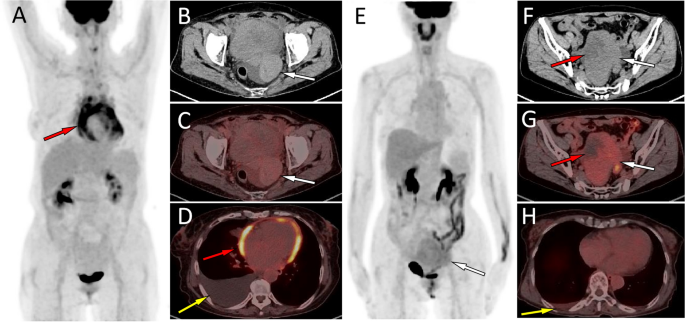

(A–D) Representative 18F-FDG PET/CT images of theca fibroma in a 72-year-old woman who sought medical help for two weeks because of pain in the precordial area and difficulty breathing. The maximum intensity projection (MIP, A) showed no significant increase in 18F-FDG uptake in the rest of the body except in the pericardial area (red arrow). Axial CT (B, arrow) showed a mass of first order soft tissue density on the left side of the pelvic cavity, and no significant uptake of 18F-FDG was observed on the corresponding PET/CT fusion (C, arrow). Axial PET/CT reveals that the lesions shown on the MIP map are pericardial effusions with increased diffuse uptake of 18F-FDG (D, red arrow). In addition, an intermediate pleural effusion without increased uptake of 18F-FDG was seen in the right thoracic cavity (D, yellow arrow). (E–H) Representative 18F-FDG PET/CT images of granulosa cell tumor (adults type) in a 45-year-old woman who sought medical attention for one month due to right chest pain. The MIP map shows a shadow with slightly increased 18F-FDG uptake in the lower abdomen (E, arrow). Axial CT (F) showed that the lesion was a soft tissue mass (white arrow) with low density cystic degeneration (red arrow) in the pelvic cavity. The axial PET/CT (G) of the corresponding site showed a mild increase in 18F-FDG uptake in the solid part (white arrow) of the tumor, with a SUVmax of 2.4, while no radioactive uptake was observed in the cystic area (red arrow). Axial PET/CT at the chest level showed a small amount of fluid in the right thoracic cavity without radioactive uptake (H, yellow arrow), and the amount of fluid accumulation is significantly lower than the amount of fluid accumulation in the serous cavity caused by serous cavity effusion.